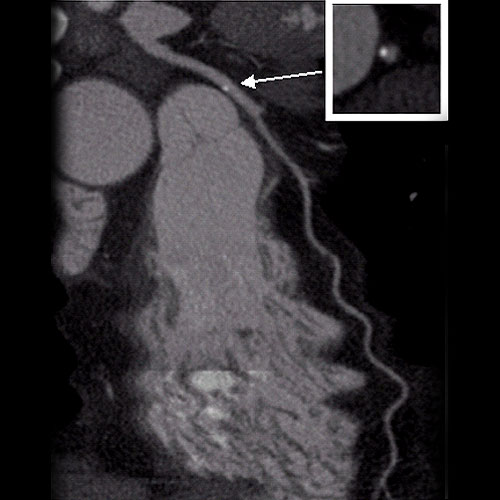

We utilize one of the few 64 slice CT scanners in North Texas that allows non-invasive diagnosis of such conditions as coronary artery disease (heart vessel blockage).  The heart vessels are displayed on our advanced 3D computer workstations where one of our doctors can make a diagnosis in minutes.  This procedure is much safer than cardiac catheterization.